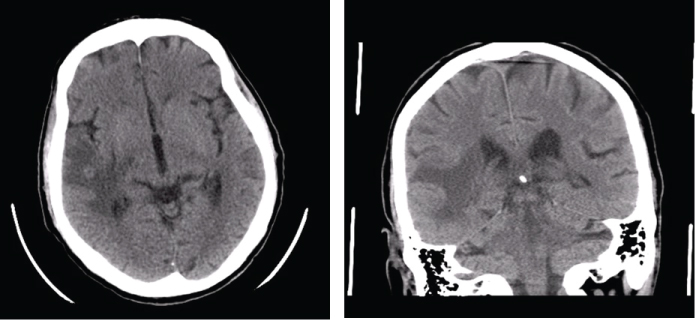

Five months after the diagnosis, he was rushed to emergency hospital with tonic-clonic seizures and a head CT revealed a "right subcortical temporal hyperdense expansive lesion, with central necrosis and peri lesional edema" (Figure 4). This was further confirmed by magnetic resonance (MRI), which also excluded secondary lesions (Figure 5).

Figure 4: Head CT: right subcortical temporal hyperdense expansive lesion, with central necrosis and peri lesional edema. View Figure 4

Figure 5: Head MRI: intra-axial lesion, round, 13 mm diameter, cortical-subcortical transition of anterior region of the right superior temporal circumvallation. The aspect is solid, hipointense on T1 (A) and isointense with grey substance on T2 (B), with moderate reinforce with gadolinium injection. Extensive perilesional vasogenic edema on the right temporal lobe. View Figure 5

The tumor was restaged as stage IV. He was submitted to metastasis ablation with gamma knife radiosurgery, however there was progression of the lesion on subsequent head CT’s. Once again, he presented with polyarthritis of hands and wrists and proximal muscle weakness of the scapular belt, which maintained.